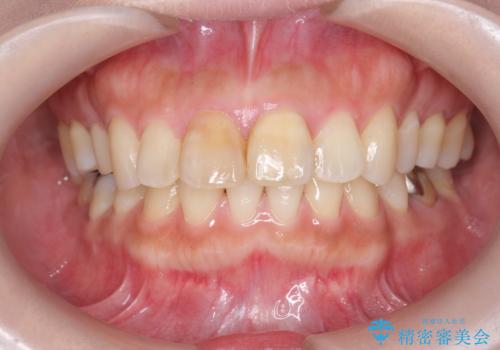

リアルな歯の色調にこだわるオールセラミッククラウン治療

- 歯の神経を除去したのちの、変色の改善を希望され来院されました。

再度根管治療を行ったのちの、オールセラミッククラン治療を計画します。

色調の再現に優れるオールセラミッククラウン スペシャルプランでの治療を希望されました。(保証5年間)

天然歯を再現したリアルな仕上がりに満足いただくことができました。

オールセラミッククラウン スペシャルプランは細やかな色調の再現に優れ、目立つ前歯の審美的な仕上がりがより達成されやすいプランです。